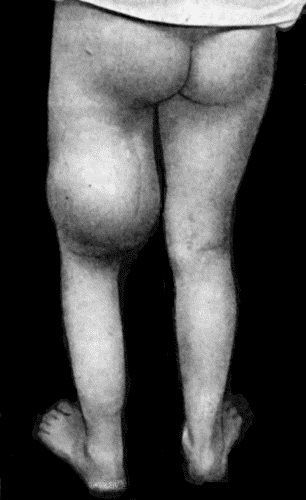

135.Cadaver, illustrating the alterations in the Lower Limbs resulting from Ostitis Deformans 475